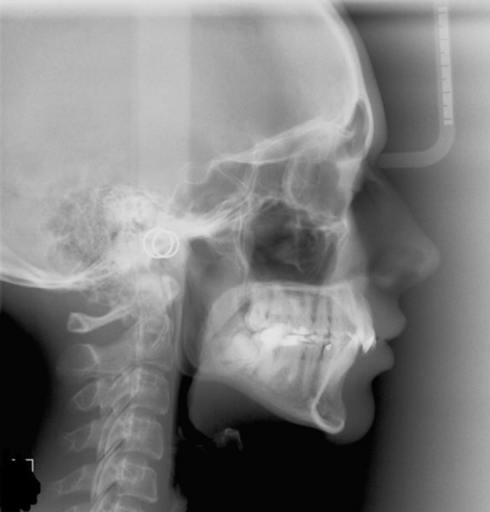

Lower Mandibular Advance after Braces?

Back 6 years ago I had braces put on and then I had them removed after they fixed my malocclusion. Before I had the braces I had an severe overbite and before I had the braces put on I had the option to have a lower jaw advancement surgery in order to line my upper and lower jaw properly, however I was young and begged my parents not to have surgery done and they agreed. After the braces I wish that I would have had the low mandibular advance because now I have a weak chin and a weak jawline. Is it possible for me to have the jaw advancement surgery done even though I have already had my braces. I would not mind getting braces back on if it meant that I was able to have the surgery. When I bring my lower jaw forward it makes my face look so much better because it correctly defines my jawline and chin(I think it makes my face how it should look. I have been looking around and saw that my orthodontist took a common root for camouflaging a larger problem. My orthodontist removed two upper teeth before I had braces put on and then he proceeded to straighten the teeth. After that he used rubber bands to bring the teeth into a somewhat correct bite(I still have a slight overbite). I don\'t think my upper and lower jaw are lined up correctly after this method of braces which is why my jawline and chin appear to be weak. Is it possible for me to have jaw advancement surgery still?